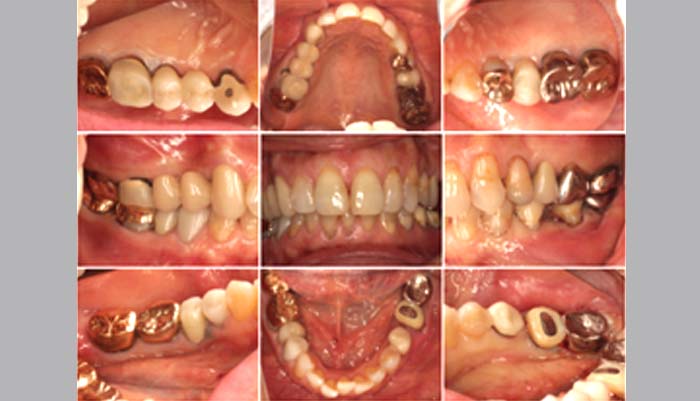

治療前